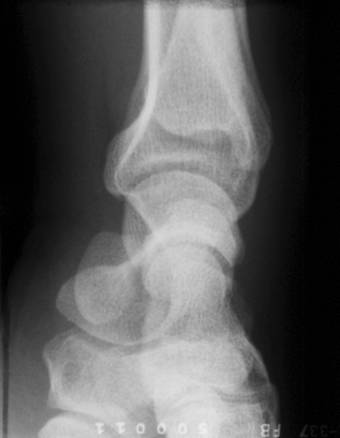

GLEZNA

Radiografia clasica

Radiografia de fata se efectueaza cu membrul inferior in extensie si glezna sprijinita de caseta port-film; fasciculul de raze este perpendicular si "tinteste" intre cele doua maleole (fig. 13).

In acest mod este posibila recunoasterea urmatoarelor structuri anatomice:

extremitatea distala a tibiei care prezinta: maleola mediala, suprafata articulara talara, fateta articulara fibulara;

extremitatea distala a fibulei cu maleola laterala mai jos situata decat cea mediala si o fateta articulara pentru apofiza laterala a talusului;

spatiul articular situat intre tibie, peroneu si talus, cu o inaltime normala de cca 3-4 mm;

suprafetele articulare ale corpului osului talus.

Radiografia de profil se executa cu fata laterala a gleznei sprijinita de caseta port-film si fasciculul de radiatii perpendicular. Pe o astfel de radiografie se pot evidentia:

epifizele distale ale tibiei si peroneului;

conturul suprafetelor articulare;

maleolele partial proiectate peste talus;

osul talus cu trohleea, corpul, colul, capul si apofizele articulare;

calcaneul cu fetele articulare pentru talus si cuboid.

Fig. 13 - Radiografie a gleznei de fata si profil